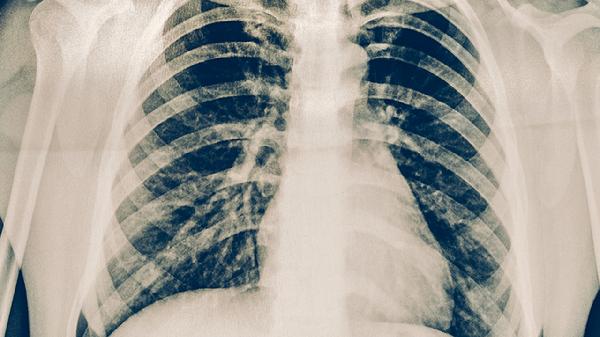

肺结核患者吃药期间不能熬夜,主要与药物代谢效率下降、免疫功能受损、治疗周期延长、耐药风险增加、症状加重等因素有关。抗结核药物需要规律作息保障药效,熬夜会干扰肝脏代谢并削弱免疫防御。

肺结核患者应保持每天7-8小时深度睡眠,服药时间固定于晨起空腹或睡前2小时。饮食需增加优质蛋白如鸡蛋、鱼肉摄入,避免高脂饮食影响利福平吸收。适当进行八段锦等温和运动,但须避免剧烈活动耗氧。治疗期间每月复查肝功能,出现视物模糊等乙胺丁醇不良反应需立即就诊。室内保持通风换气,家属应协助监督用药并观察痰液性状变化。